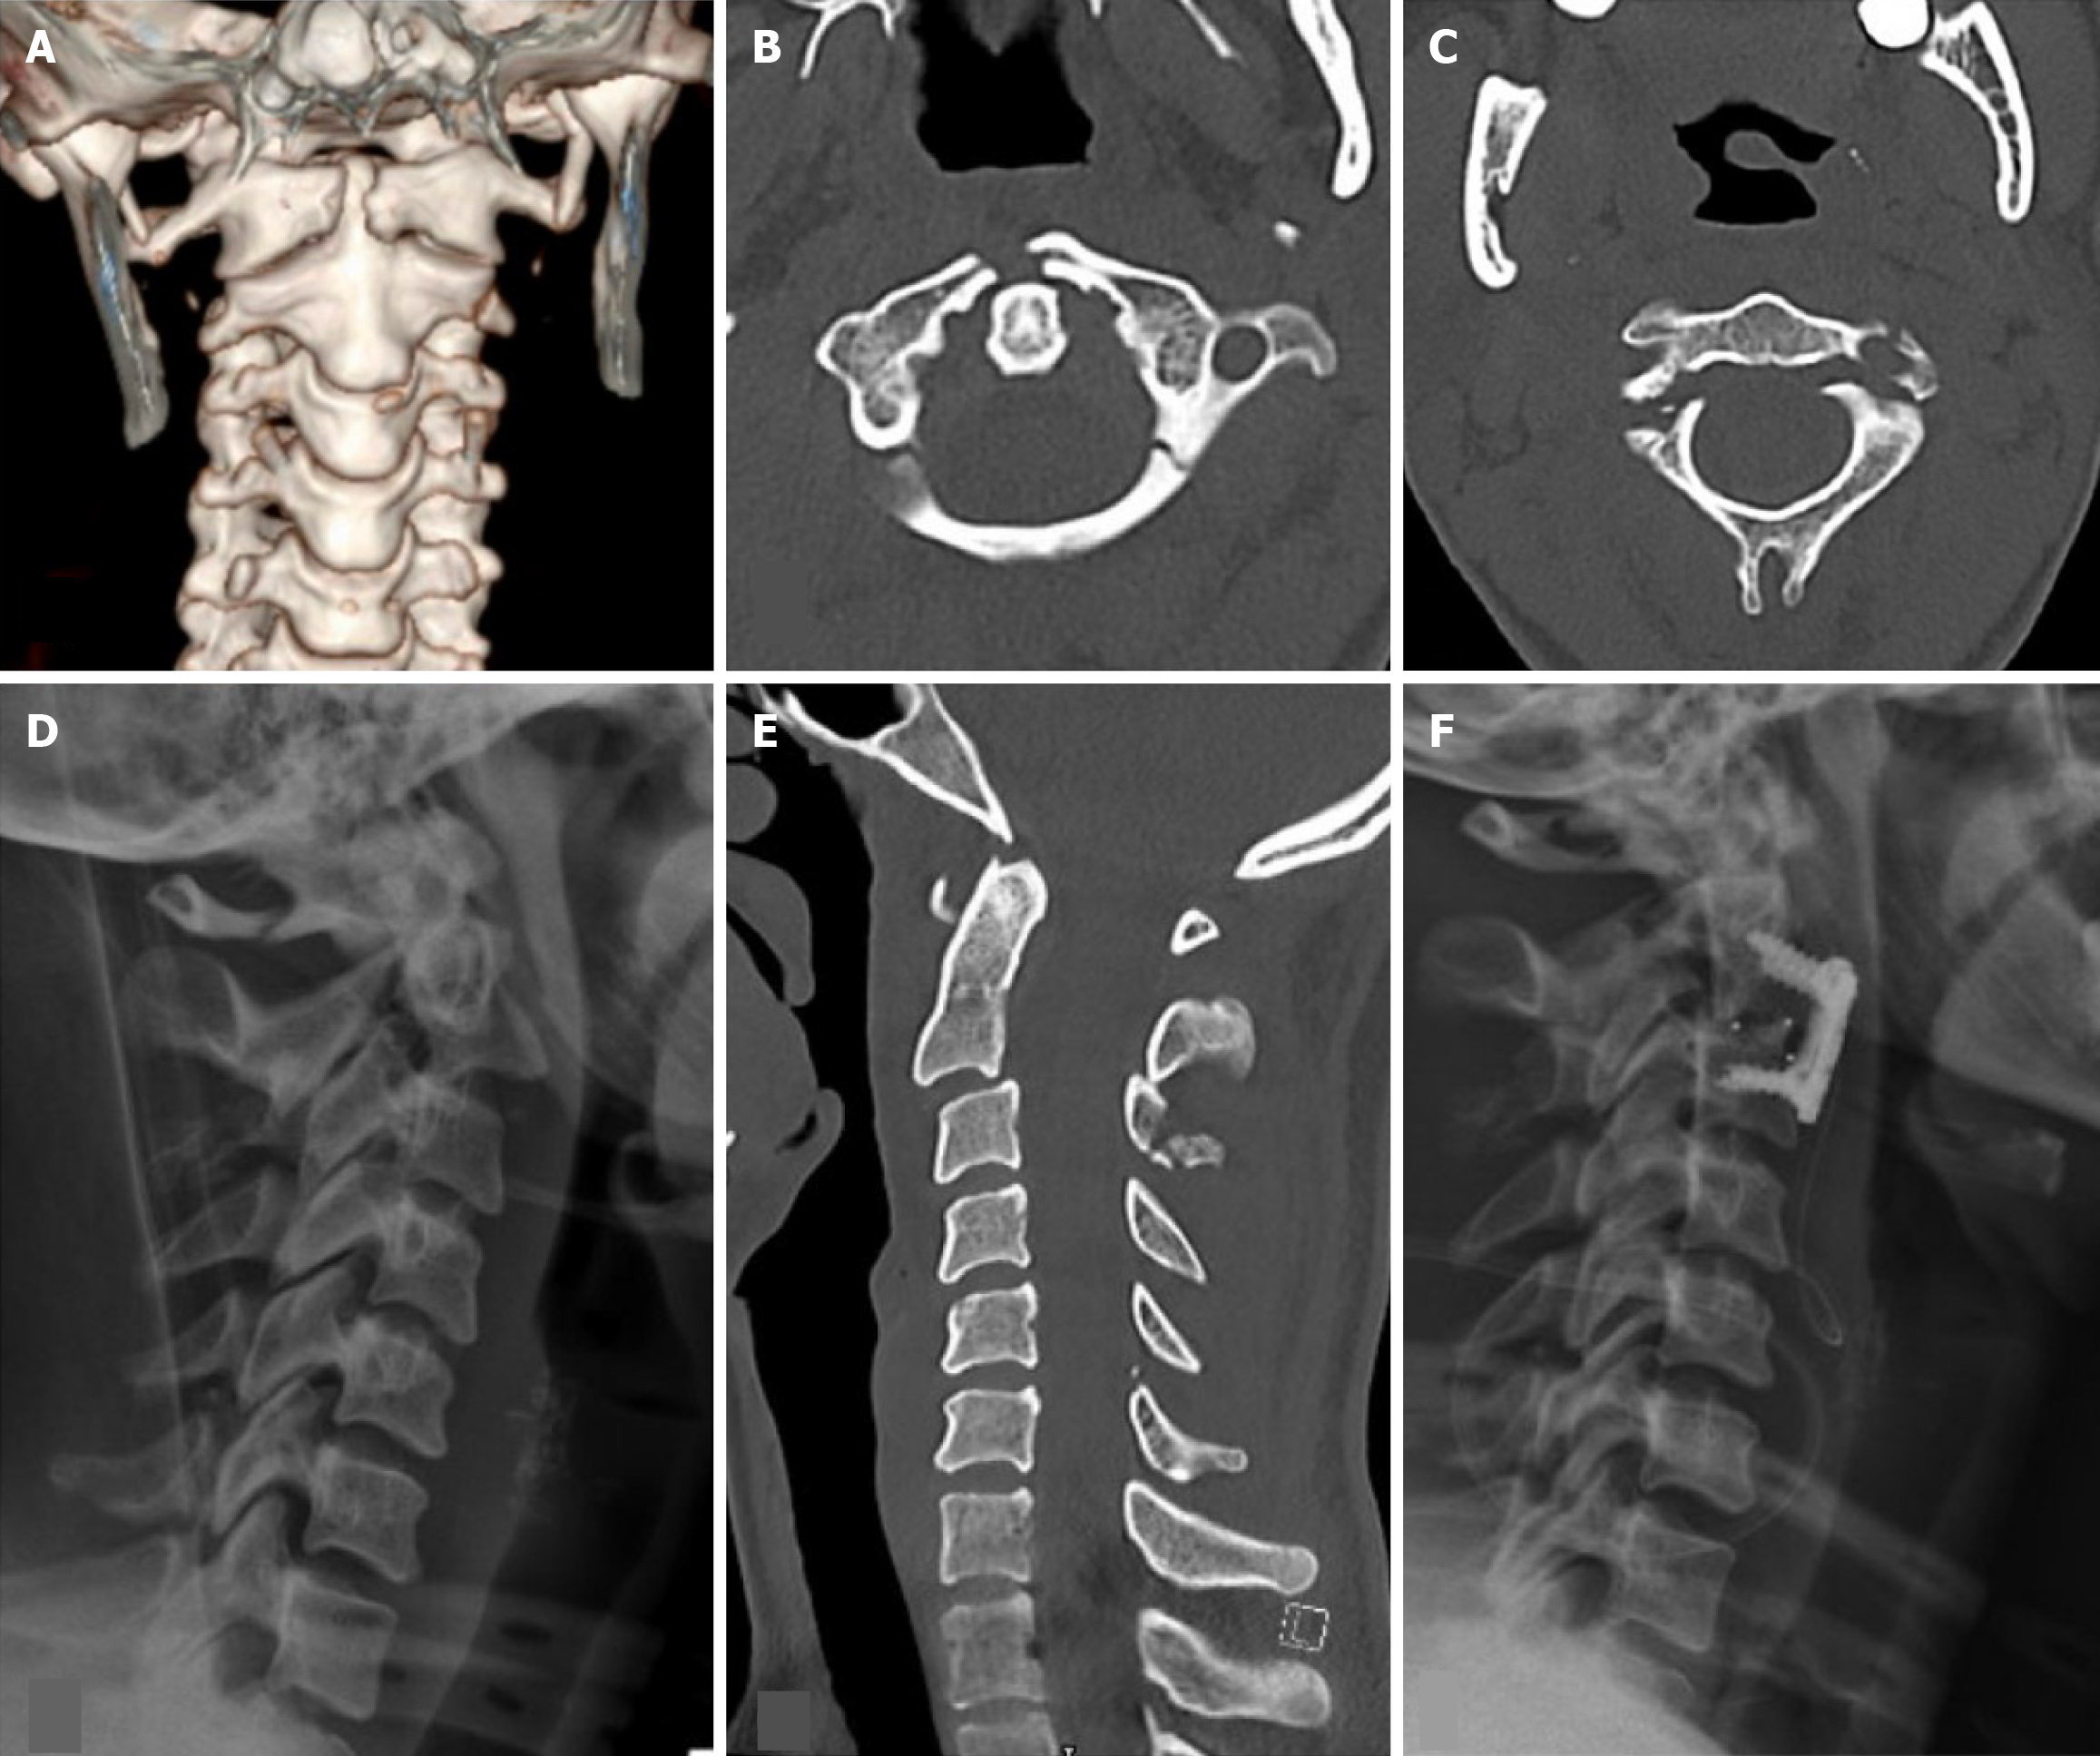

Case 3: The e-FAST was negative, and chest and pelvic X-rays were normal. A pan-CT scan revealed a Jefferson fracture (Figure 3A and B) of the first cervical vertebra (C1), a Hangman fracture (Figure 3C) of the second cervical vertebra (C2) with grade I spondylolisthesis of C2 over C3 (Figure 3D and E), a right facet joint fracture at C6-C7, and a fracture of the anterosuperior endplate of the fourth thoracic vertebra (T4). MRI confirmed these spinal injuries, along with disruption of the anterior Atlanto-occipital membrane on the right, injuries to the apical, transverse, and anterior longitudinal ligaments. Additional injuries included bilateral lung contusions.

She was admitted to the Trauma Intensive Care Unit, initially managed with a halo vest, and underwent C2-C3 ACDF three days later (Figure 3F). She was discharged ten days after admission. The pattern of injuries reflects a combined high-energy axial and hyperextension-flexion mechanism. The Jefferson fracture resulted from axial loading via the occipital condyles. The Hangman fracture with grade I spondylolisthesis reflects a classic hyperextension-distraction mechanism involving posterior tension and anterior shear forces on the pars interarticularis. The C6-C7 facet fracture may have resulted from hyperflexion with shear, while the T4 endplate fracture likely resulted from localized axial compression. The ligamentous injuries confirmed the multi-directional nature of the forces involved, with both tensile and compressive components acting across different cervical levels. This biomechanical complexity justified the staged management: Initial halo vest immobilization, followed by definitive C2-C3 ACDF.

Anterior atlantoaxial subluxation: It occurs due to a flexion/shear force that disrupts the transverse ligament of the atlas[12] and is an infrequent injury. Such injuries can occur in motor vehicle crashes and tackling during football play. The second case in our series sustained the C1 and C2 fracture and grade 1 spondylolisthesis. He has a disruption of the anterior atlantooccipital membrane and anterior longitudinal ligament with injury to the nuchal and interspinous ligaments. Another patient (case 3) in our series has a Jefferson fracture (Figure 3) and a Hangman fracture (Figure 3). MRI of the spine showed disruption of the anterior atlantooccipital membrane on the right, injury to the apical ligament, transverse ligament, and anterior longitudinal ligament.

Traumatic spondylolisthesis: This type of injury results from the extension and distraction of the cervical spine and occurs when there is a hyperextension force centered on the chin or during judicial hanging. The hyperextension caused a fracture of the pars interarticularis of C2. This type of injury can also lead to PLL disruption, C2-C3 intervertebral disc damage, and bilateral facet fractures/dislocations[14]. It is also called a Hangman’s fracture; however, the most common cause is motor vehicle accidents. One patient (case two) in our series had grade 1 spondylolisthesis of C6 over C7, along with Hangman fracture and other spinal injuries. This patient was neurologically intact and was managed with a halo vest application and C2-C3 ACDF.

C1 fracture: The fracture of the atlas constitutes about 2%-13% of all cervical spine injuries and is typically associated with the traumatic axial loading of the head on the lateral masses of C1[15]. This type of injury causes Jefferson fractures, a burst-type fracture of C1 with bilateral fractures of the anterior and posterior arches of the atlas. Other external forces can be applied during this type of fracture, which includes flexion, extension, and rotatory forces. Sometimes, the isolated anterior or posterior arch fractures or a unilateral lateral mass fracture can occur, depending on the combination of forces applied concomitantly with the axial compression[16]. The treatment of this fracture depends on the mechanical stability and neurological status. If the transverse ligament is intact, the injury can be managed with a stiff collar or halo immobilization. If the ligament is injured, treatment will include a C1-C2 fusion or an occipito-cervical fusion. Two of our patients (cases two and three), who were unrestrained back-seat passengers, sustained a Jefferson fracture along with other cervical spine injuries (Figures 2 and 4). Both patients had no neurological deficit and were managed with a halo vest application.